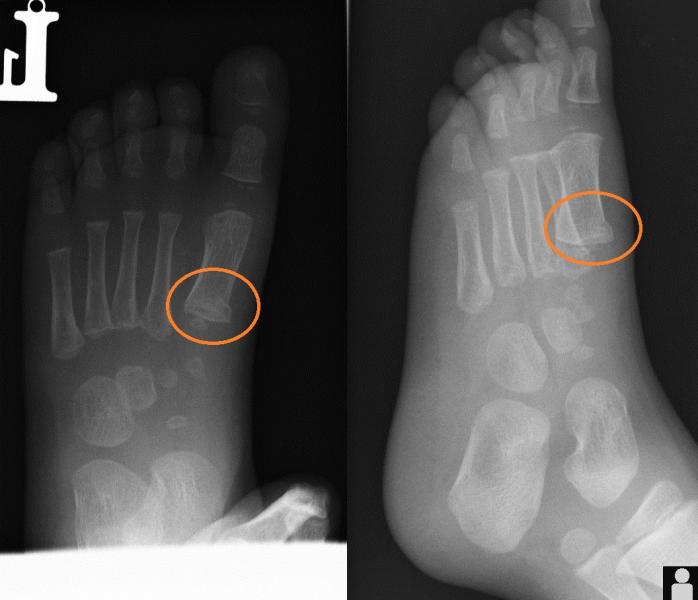

Przypadek 3: 2-letni chłopiec po urazie śródstopia lewego. Chód utykający, niewielki obrzek grzbietu stopy lewej.

Rozpoznanie: Złamanie podokostnowe przynasady bliższej I-ej kości śródstopia lewego.